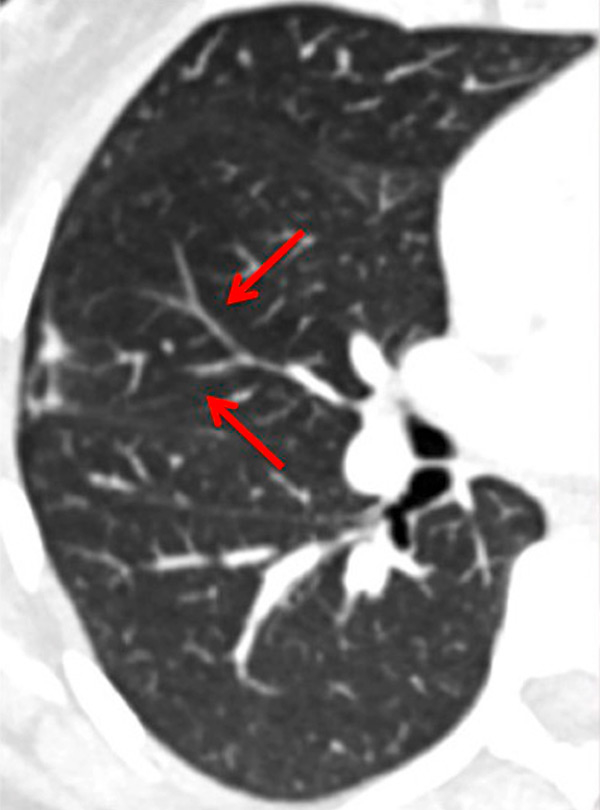

Figure 10

Severe bronchopathy (arrow) in the left lower lobe (A) associated with extended hypoperfusion (arrow) and dilatation of the right cardiac cavities (stars) (B).